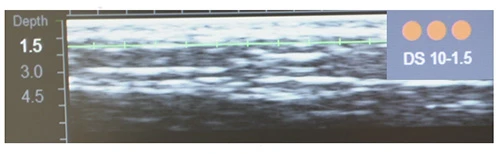

Диагностическая визуализация. Протокол лечения: DS 7–4,5 60 линий, DS 7–3,0 600 линий; DS 10–1,5 60 линий. Суммарно все лицо, включая субментальную зону: 720 линий.